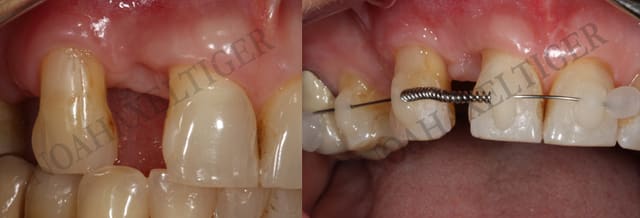

Ca y est ... mes 3 premiers cas de Dancha en pré implantaire.

Je sais je vais me faire lapider et critiquer mais c'est bien pour ca que je vous montre ces 3 cas.

je suis ouvert à toutes critiques à partir du moment où elles sont contructives ;-))

contrôle à 1 mois du cas numero 2. Tout marche comme prévu. Encore mille mercis Daniel. Ta technique a beaucoup plus à mes confrères suédois !

Cas nr 2 controle  1mois kps86j - Eugenol